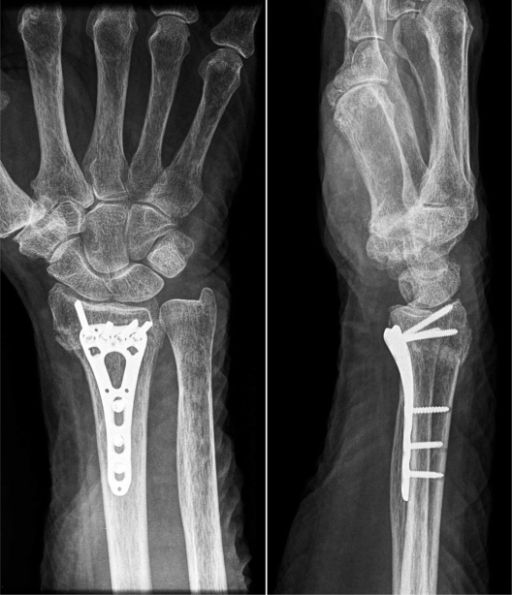

Upper limb fractures and dislocations

Upper limb refers to part of our body starting from the shoulder upto the fingers in our hands. As we use the arms and hands for routine and recreational activities like sports, they are prone for several injuries including fractures (break in the bone) or dislocations (loss of alignment of joints like shoulder / elbow) resulting in sever pain and sometimes risk to the arm / hand survival.

Rapid diagnosis and immediate treatment from a specialist like Dr Darshan Angadi who is well experienced in managing these injuries is crucial to prevent the risk of long-term complications that can occur from damage to nerve / tendon / artery or cartilage.